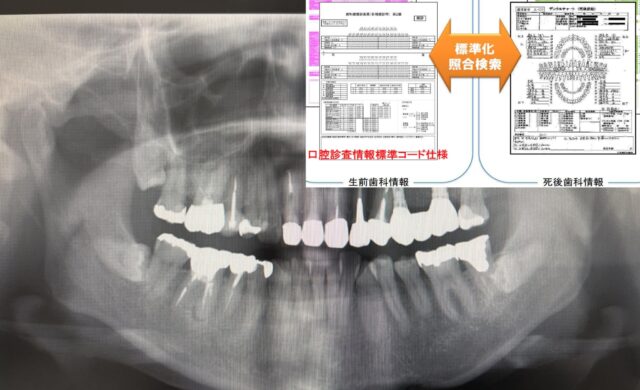

東日本大震災の経験から、国は歯科情報の利活用を進め、「口腔診査情報標準コード仕様」を構築し、厚労省標準規格として認定しています。

生前歯科情報と死後歯科情報を“同じ言語(標準コード)”に翻訳し、検索・照合可能にすることが鍵になります。

現実的なワークフロー:「標準化 → 照合検索 → 人が最終判断」

- 生前データを標準化

パノラマ画像をAIで解析し、歯式を構造化(標準コード仕様にマッピング) - 死後データを標準化

検視時の歯科所見/死後画像(デンタル・パノラマ相当、あるいはCT由来画像)を同じ形式へ - 照合検索で候補を上位提示

「多数の対象から候補を数%まで絞る」 - 歯科医師が最終鑑定

候補上位に対して、補綴物の詳細、治療痕、骨形態などを総合して最終判断